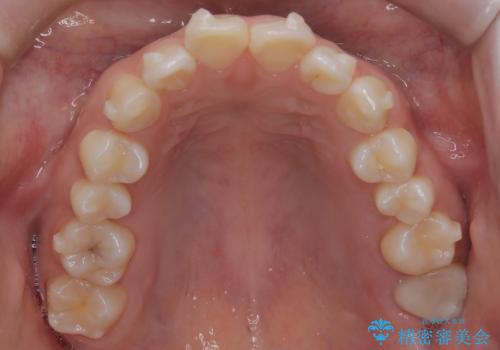

- 前歯のデコボコ(叢生)を気にされてご来院されました。精密な検査の結果、歯が並ぶスペースが不足していることが判明。患者様のご希望から、透明で目立ちにくいインビザライン(マウスピース矯正)による治療計画を立案しました。抜歯を避け、奥歯全体を奥へ動かす遠心移動という方法でスペースを確保し、前歯の叢生を解消することを目指します。

今回の矯正治療では、透明なマウスピース型の装置インビザラインを使用しました。この装置は取り外し可能で、日常生活で目立ちません。治療は、緻密に計算された計画に基づき、段階的に作製されたマウスピースを交換していくことで、奥歯から順に全体を後方へ移動させる遠心移動を実施。これにより、前歯を並べるための十分なスペースが確保され、デコボコが解消されました。抜歯することなく、機能的にも審美的にも整った美しい歯並びを獲得していただけました。